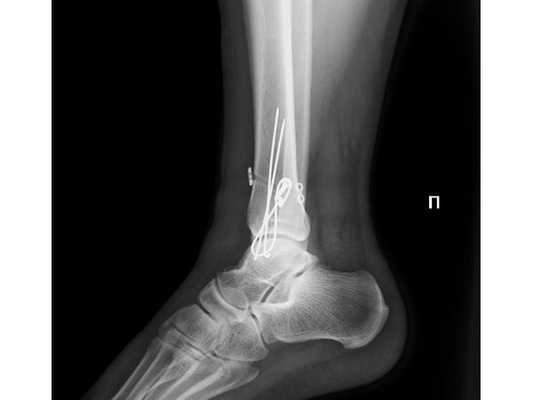

После обследования и уменьшения отёка мягких тканей на четвёртые сутки с момента травмы больному проведено оперативное вмешательство. Под спинномозговой анестезией выполнена открытая репозиция перелома внутренней лодыжки правой голени спицами и стягивающей проволочной петлёй, фиксация дистального межберцового синдесмоза стягивающей петлёй с упорными металлическими площадками.

Ранний послеоперационный период протекал без осложнений. На третьи сутки после операции конечность фиксирована гипсовой повязкой от нижней трети правого бедра до плюснефаланговых суставов. Пациент активизирован с опорой на костыли без нагрузки на правую нижнюю конечность. Выписан на амбулаторное долечивание под наблюдение районного травмпункта.

- Ходьба с опорой на костыли без нагрузки на правую нижнюю конечность в течение 6-8 недель с момента операции.

- Гипсовая иммобилизация правой нижней конечности в течение 6-8 недель.

- Рентгенография правого голеностопного сустава через 4, 8, 12 недель с момента операции.